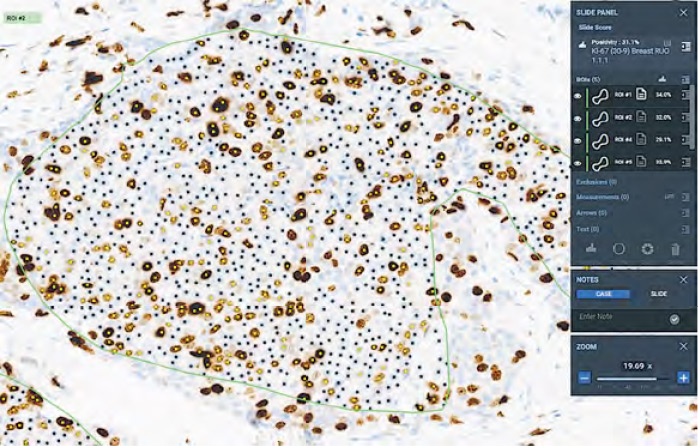

該兩院病理學部門將化驗樣本數字病理化後,亦購入AI軟件,試行以AI輔助為乳癌及前列腺癌診斷,計劃明年2至3月開始使用,用途包括點算乳腺癌細胞,並以AI標示前列腺組織樣本病變情况。

購AI軟件助診斷癌症

陳昌堅說,兩院每周約有6個前列腺及10個乳癌樣本需診斷,以往病理科醫生需花時間點算癌細胞,希望AI可加快工作流程,而AI亦可於工作列表當中,優先標示患癌樣本。他說日後亦擬將AI應用於胃部、淋巴組織診斷,並自行開發AI工具。

「AI唔肯講唔識」 仍有「甩漏」

被問到AI輔助診斷病理報告的準確度,陳昌堅說AI大部分時間準確,但不同場景使用時可能會有「甩漏」,亦可能「寧願噏錯啲嘢,都唔肯同你講佢唔識」。他說會先做測試及認證才開始使用AI診斷,短期內不會讓AI自行發出化驗報告,醫生仍需就診斷作獨立決定,向病人提供最好治療方案。